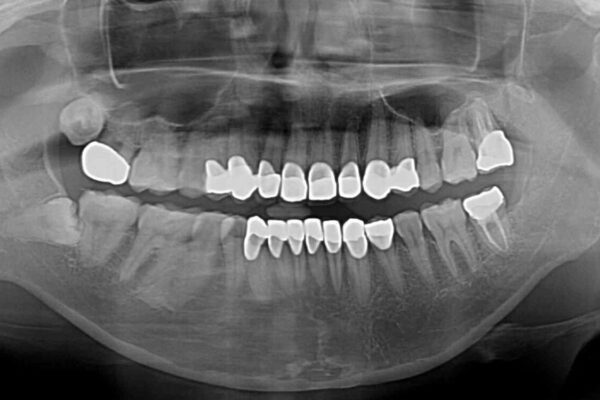

全顎的にむし歯が多く、根管治療の必要な奥歯や、審美的に気になっている前歯を中心にオールセラミッククラウンにて補綴治療を行うこととしました。

上顎前歯は歯肉退縮により歯根が露出していたため、事前に歯肉移植術により根面被覆を行い、その後にオールセラミッククラウンを装着することとしました。

治療途中

• むし歯だらけの前歯をオールセラミッククラウンできれいに 治療途中画像